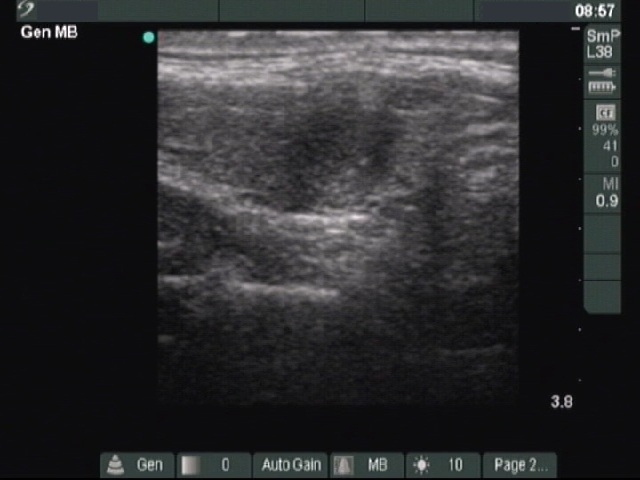

Benign nodular hyperplasia - Case 43. |

Clinical presentation: a 26-year-old woman was presented with a newly discovered nodule.

Palpation: a nodule in the right side of the isthmus.

Functional state: euthyroidism with TSH-level of 1.56 mIU/L.

Ultrasonography: a moderately hypoechogenic nodule in the isthmus. The nodule exhibited microcalcifications. The vascularization was not specific. Neither a halo sign nor perinodular blood flow was observed.